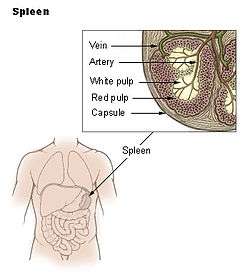

The spleen (from Greek σπλήν—splḗn[1]) is an organ found in virtually all vertebrates. Similar in structure to a large lymph node, it acts primarily as a blood filter.

The spleen plays important roles in regard to red blood cells (also referred to as erythrocytes) and the immune system.[2] It removes old red blood cells and holds a reserve of blood, which can be valuable in case of hemorrhagic shock, and also recycles iron. As a part of the mononuclear phagocyte system, it metabolizes hemoglobin removed from senescent erythrocytes. The globin portion of hemoglobin is degraded to its constitutive amino acids, and the heme portion is metabolized to bilirubin, which is removed in the liver.[3]

The spleen synthesizes antibodies in its white pulp and removes antibody-coated bacteria and antibody-coated blood cells by way of blood and lymph node circulation. A study published in 2009 using mice found that the red pulp of the spleen forms a reservoir that contains over half of the body's monocytes.[4] These monocytes, upon moving to injured tissue (such as the heart after myocardial infarction), turn into dendritic cells and macrophages while promoting tissue healing.[4][5][6] The spleen is a center of activity of the mononuclear phagocyte system and can be considered analogous to a large lymph node, as its absence causes a predisposition to certain infections.[7]

In humans, the spleen is brownish in color and is located in the left upper quadrant of the abdomen.[3][8]

Structure

The spleen, in healthy adult humans, is approximately 7 centimetres (2.8 in) to 14 centimetres (5.5 in) in length. It usually weighs between 150 grams (5.3 oz)[9] and 200 grams (7.1 oz).[10] An easy way to remember the anatomy of the spleen is the 1×3×5×7×9×11 rule. The spleen is 1" by 3" by 5", weighs approximately 7 oz, and lies between the 9th and 11th ribs on the left hand side.

Blood supply

Near the middle of the spleen lies a long fissure, the splenic hilum. The hilum is the point of attachment for the gastrosplenic ligament, and the point of insertion for the splenic artery and splenic vein. There are other openings present for lymphatic vessels and nerves.

Like the thymus, the spleen possesses only efferent lymphatic vessels. The spleen is part of the lymphatic system. Both the short gastric arteries and the splenic artery supply it with blood.[11]